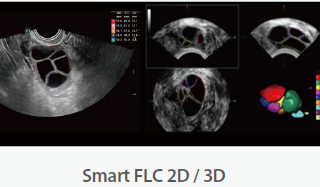

Mindray Ultrasound Consona N9